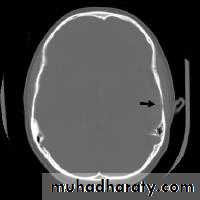

EDH

Biconvex hyper density area

Shifting of the midline

Compression of the ventricles